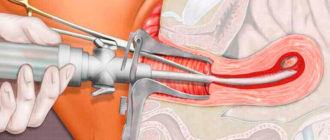

Резектоскопия миомы матки Содержимое 1 Применение методов в современной гинекологии 2 Проведение Миома матки

Аспирационная биопсия эндометрия: как проводится, подготовка, больно или нет, последствия Аспирационная биопсия эндометрия, или